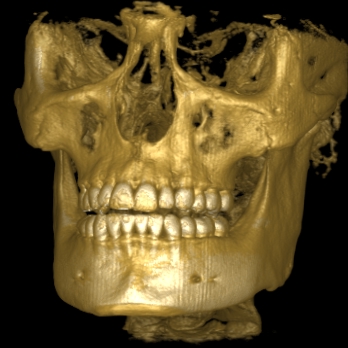

Im folgendem sehen Sie die Darstellung eines Teils des menschlichen Schädels mit Lokalisation des Nervkanales.

Frontalansicht |

3D-Darstellung |